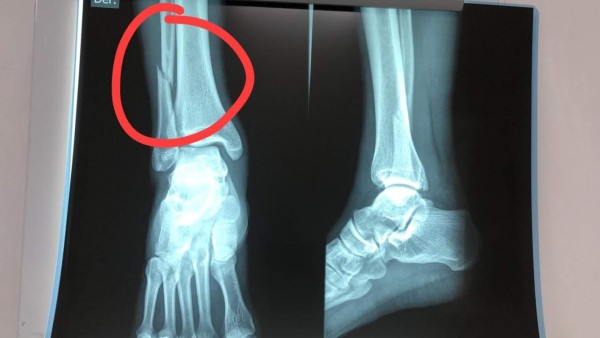

Estas son las radiografías del futbolista de Motagua, Erick Andino.

El mandatario de los Azules le envió un mensaje directo a Elías Burbara, presidente de Real España: 'Andino doble fractura, y creen que el árbitro solo pitó en contra, dejen de especular el árbitro pitó mal porque es malo, estas son las consecuencias de no tener autoridad en la cancha'.